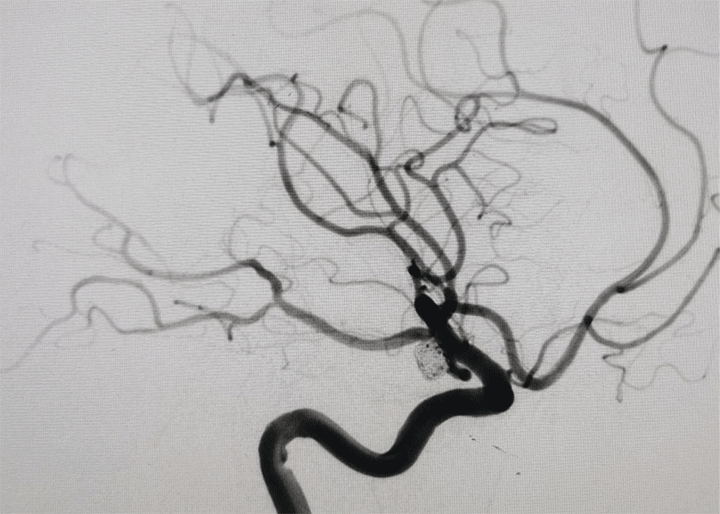

入院后吴全主任立即安排科室医生陪同患者紧急行头颅CTA检查提示双侧后交通动脉瘤破裂出血,结合头颅CT,考虑右侧后交通动脉瘤为责任动脉瘤。患者为镜像动脉瘤,很少见,一侧动脉瘤破裂出血,另一侧也有破裂出血的风险。

手术中造影可见右侧动脉瘤破裂小泡,为责任动脉瘤,术中予以支架辅助栓塞,考虑患者血管条件极差,若左侧同期处理,手术时间较长,容易形成血栓,增加手术风险,团队决定先处理责任动脉瘤,左侧后交通动脉瘤择期处理。